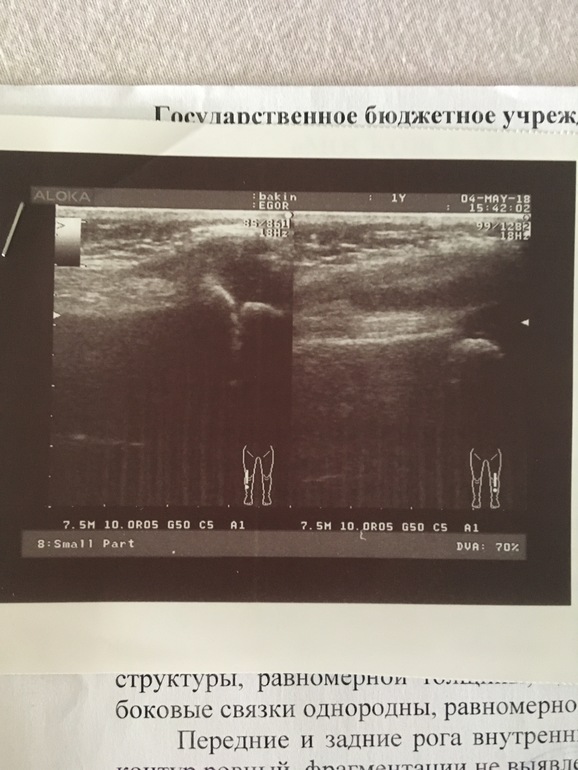

ортопед послал не рентген, на рентгене все хорошо, дал направление в ортопедическую больницу в Москве, приехали туда нам сделали УЗИ и сказали то что это реактивный артрит, посоветовали найти хорошего врача ревматолога, мы поехали к кардиоревматологу, он нам выписал какие необходимо сдать анализы, мы их сдали , результаты скоро будут готовы, лечение назначено,